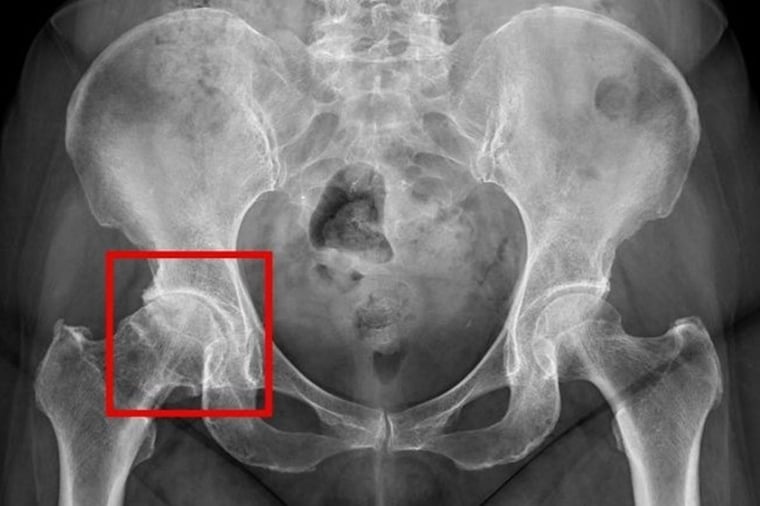

黃振文指出,髖關節是人體中最大的負重關節之一,由骨盆的髖臼與大腿骨頂端的股骨頭所構成,屬於穩定度高、活動範圍廣的球窩關節。其表面覆蓋著光滑的軟骨,可有效減少日常活動中的摩擦並吸收衝擊。一旦軟骨因老化、長期磨損或外傷受損時,便可能導致骨頭間直接摩擦,引發發炎與疼痛。初期症狀多在活動時才出現,但隨著病情加劇,疼痛可能在休息或夜間也會持續,無法緩解。

臨床上,患者常會出現鼠蹊部、大腿內側或下背部疼痛,並伴隨關節僵硬或有「喀喀」聲,使活動受限或是出現跛行的情形。至於需要進行人工髖關節置換的常見原因包括:退化性關節炎、股骨頭缺血性壞死、嚴重髖部骨折或先天結構異常等,其中又以退化性關節炎為主要原因。黃振文說,退化性關節炎屬於逐步惡化且不可逆的疾病,若長期未接受治療,可能因疼痛減少活動,導致周邊肌肉萎縮、行動能力下降,嚴重者甚至需要長期臥床。

在治療上,髖關節疼痛初期多採保守治療為主,包括休息、使用消炎止痛藥物、熱敷、電療或減重,藉此減輕疼痛、維持關節活動度及延緩退化。針對嚴重髖關節退化的患者,人工髖關節置換手術則為主要治療方式。醫師會在術前透過X光等影像檢查,評估關節磨損程度與骨骼狀況,以規劃適合的手術方式。